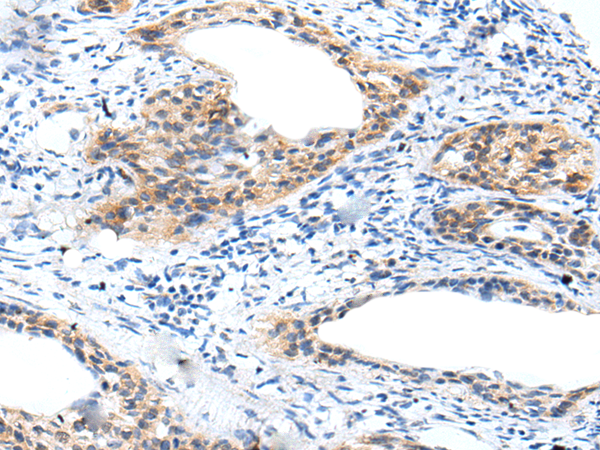

IHC positive control: |

Human cervical cancer |

IHC Recommend dilution: |

10-50 |